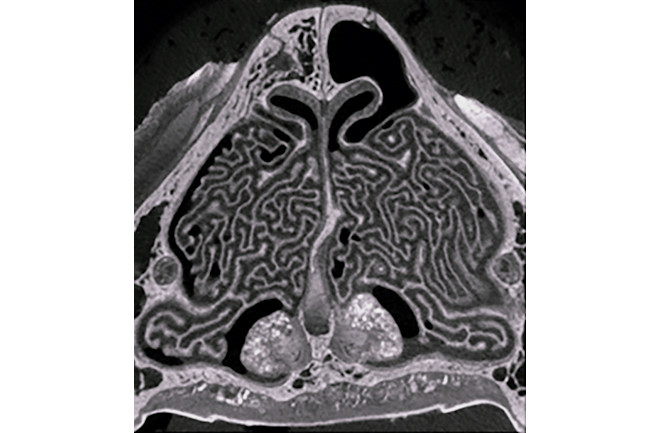

Студијата ја мапираше оваа сложена мрежа со КТ скенирање на трупот на домашна мачка со кратки влакна, откривајќи ги сложените набори и премини кои се навиваат низ етмоидната коска на мачката. Луѓето исто така имаат турбини, но нашите се состојат од неколку поедноставени набори, а ние имаме релативно слабо сетило за мирис за да се совпаднеме.